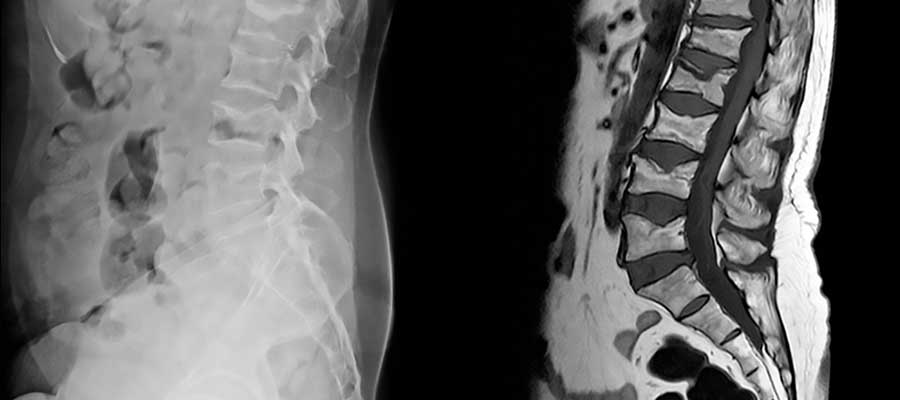

Magnetic Resonance Imaging (MRI) is actually a medical imaging way that is utilized in radiology within the formation of physiological and anatomic body processes. MRI scanners employ radio waves, magnetic field gradients and robust magnetic fields to produce body organ images. That is why, a licensed MRI technologist is needed to capture the photos the doctor needs.